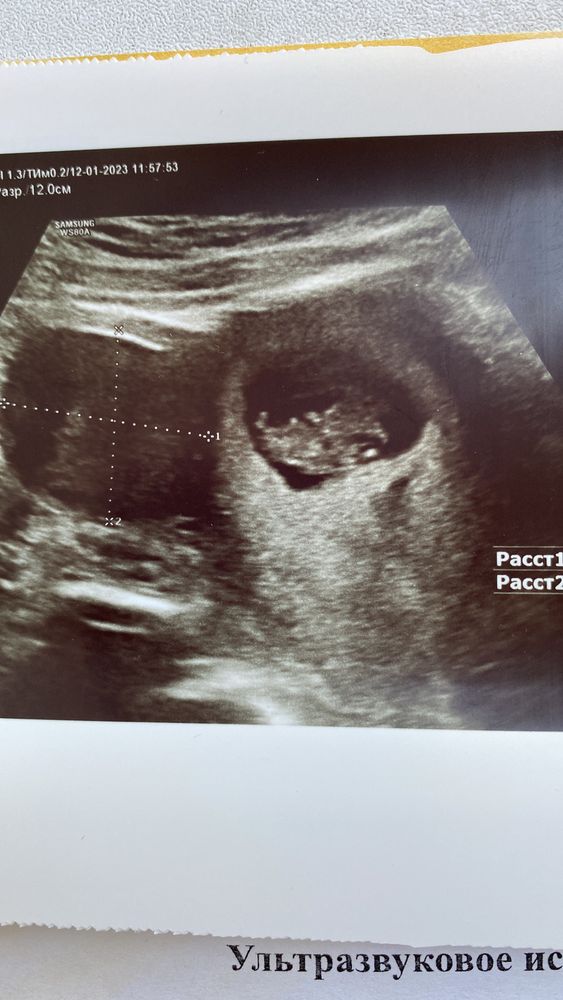

Я вас так хорошо понимаю.. Мне 38,третий брак и счастливый. Есть дочка от второго 7 лет. В ночь со 2го на 3е января у меня случился выкидыш на 11 ой неделе. Уже было сердцебиение, хороший эмбрион и вообще все шло хорошо, а потом вот так. Учитывая то, что я вообще не знала, что оказывается на 10 беременностей приходится 3 выкидыша, я тоже была в ступоре. Аспирация под наркозом, пустота, 2 дня ничего не ела, жить не хотелось.. Спасибо мужу, поддержал, близким, так помогли. У моей подруги было 3 выкидыша +1 вб, потом сын, потом опять выкидыш, потом ещё сын и вот опять беременна. Я вас обнимаю крепко, дай Бог вам веры и сил, мне кажется у вас все получится, обратитесь к Матронушке, съездите к её мощам в Москве. И верьте. У вас нелёгкий путь, у всех он разный, но всегда заканчивается успехом, кто хочет, верит и все равно идёт вперёд. 🙏🙏🙏

Итог эко - зб Замершая беременность после эко